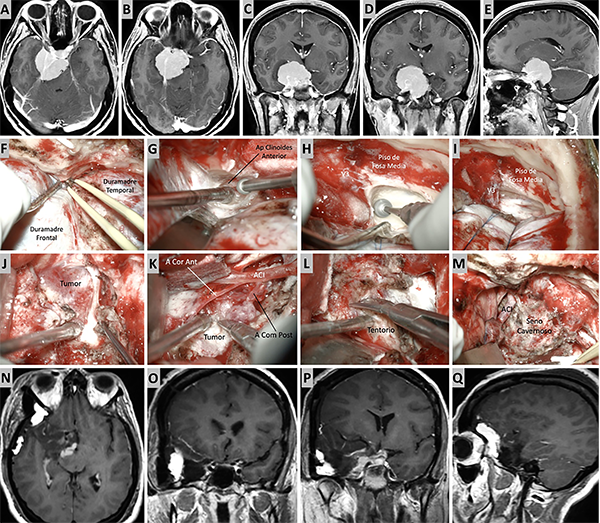

Figura 11. Caso ilustrativo #9. A-D. Imagen por RMN que muestran MRPC con implantación petroclival, extensión a la fosa craneal media y clinoides anterior. F-L. Se realizo un abordaje combinado con clinoidectomia anterior extradural y petrosectomia anterior. N-Q. Se consiguió una resección casi total. Imágenes postquirúrgica por RMN.